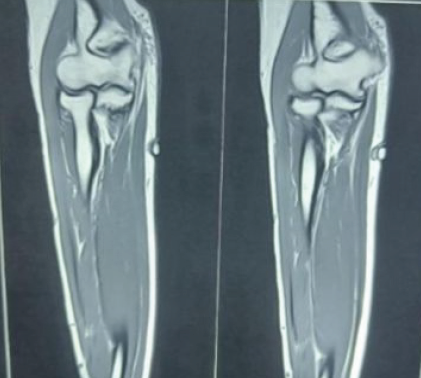

Clinical examination revealed a well-defined, soft, bluish papule over the medial forearm. The lesion was approximately half a centimeter in diameter, with marked local tenderness but no induration, temperature rise, or regional lymphadenopathy. Given the chronicity and focal nature of symptoms, a benign soft tissue tumor was suspected. Initial blood investigations were unremarkable. Ultrasonography showed a well-circumscribed hypoechoic subcutaneous lesion without vascular invasion. MRI of the forearm revealed a small, superficial, subcutaneous lesion with homogeneous post-contrast enhancement (Fig. 2). It was located close to the basilic vein, yet distinct from vascular structures, raising suspicion for a vascular tumor, possibly a glomus tumor.

Figure 2: Magnetic resonance imaging of right forearm showing a small, superficial, subcutaneous lesion with homogeneous post-contrast enhancement.